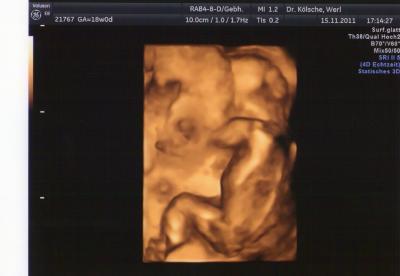

Guten Morgen meine Lieben!! Soweit war alles okay,meine Waage stimmt wohl auch irgendwie nicht ,die beim Fa hat um einiges weniger angezeigt.Gott sei Dank!!! Also erstmal das negative.Muss nun alle zwei Wochen zum Fa,weil meine blöde Plazenta noch immer komplett überm inneren Muttermund liegt .Deswegen werd ich jetzt öfters kontroliert.Hoffe echt so sehr das es nicht auf einen Ks hinaus läuft. Dann hab ich eine Überweisung bekommen.Grund :Vitium cordis . So heißt das in der Fachsprache Deswegen hab ich grade einen Termin für nächste Woche zur Feindiagnostik!!! Ansonsten war der Zwerg ordentlich am turnen....war gar nicht so leicht ihn mal zu gesicht zu bekommen.Dabei war ja die große Schwester mit.Weiß deswegen auch nur das Gewicht das war knapp über 200g Ein Outing haben wir auch bekommen Und haben uns voll vertippt....na ja geahnt hatte ich es ja schon.Wir bekommen eine Prinzessin .War echt sehr eindeutig....Und dachte echt es wird ein Junge.....:D Wohl falsch gedacht. Alles in allem war es ein schöner Termin.Anbei ist noch ein Foto.Leider hat sie nie richtig still gehalten,weil sie zu sehr mit kuscheln der Plazenta und Daumen lutschen beschäftigt war.Aber Hammer wie perfekt sie jetzt schon ist.Bin sooo verliebt. LG Vanessa

Bild zu °°°°°Gestern Fa Termin °°°°° - Forum für April - Mamis